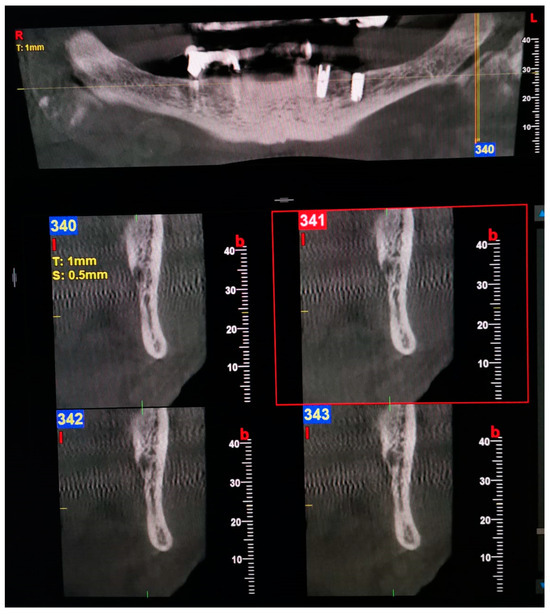

Examples of images considered positive for BMC and TMC are shown in Figure 1, Figure 2, Figure 3, Figure 4, Figure 5, Figure 6 and Figure 7. Regarding the distribution among patients, 36 subjects (15.13%) showed at least one BMC, 12 (5.04%) bilaterally, while 2 subjects (0.84%) showed a TMC. Among patients with cases considered positive for BMC, 21 were women, accounting for 8.82% of the total studied population and 14.89% of female patients overall. On the other hand, 15 BMC patients were men, accounting for 6.30% of the whole sample and 15.4% of men in the study. Considering the hemi-mandibles, BMC appeared in 9.87% of images, while TMC only appeared in 0.42%. The Patient group that was positive for BMCs had a mean age of 34 ± 13.30, while the group that was positive for TMCs presented a mean age of 43 ± 19.8. Pearson’s Chi-Square test was not significant; no association was found between gender and the prevalence of mandibular canals.

Figure 6. Panoramic view and transverse section of a left TMC. l, lingual. b, buccal. T, thickness. S, section.